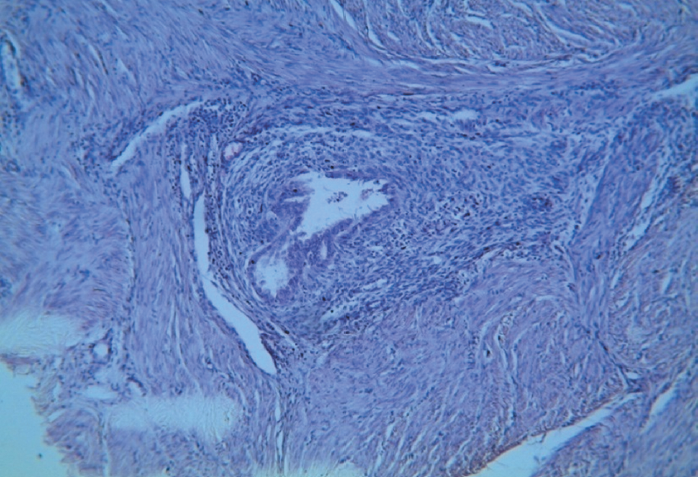

- Лейомиомы с очагами эндометриоза (рис. 4, 5). 2. Очаги эндометриоза между пучками гладкомышечных волокон (рис. 3). 3. Лютеиновая киста яичника.

Рис. 5. Склеротическая форма аденомиоза. Очаг эндометриоза в лейомиоматозной ткани. Окраска гематоксилином и эозином. Увеличение ×10

Fig. 5. Sclerotic type of adenomyosis with endometriosis foci within leiomyomatous tissue. Haematoxylin and eosin stained specimens. ×10 magnification